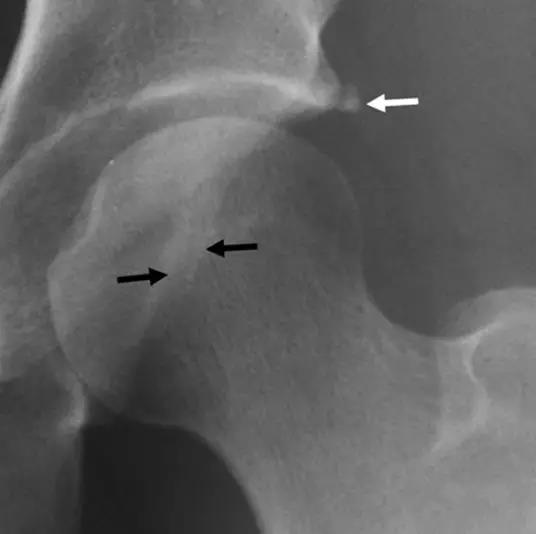

- 股骨颈疝窝

- 关节积液及滑膜增生

- 骨髓水肿MR造影优于常规MR

- 股骨头颈联合处前上缘骨性突起。

- 凸轮撞击型FAI--并盂唇撕裂。